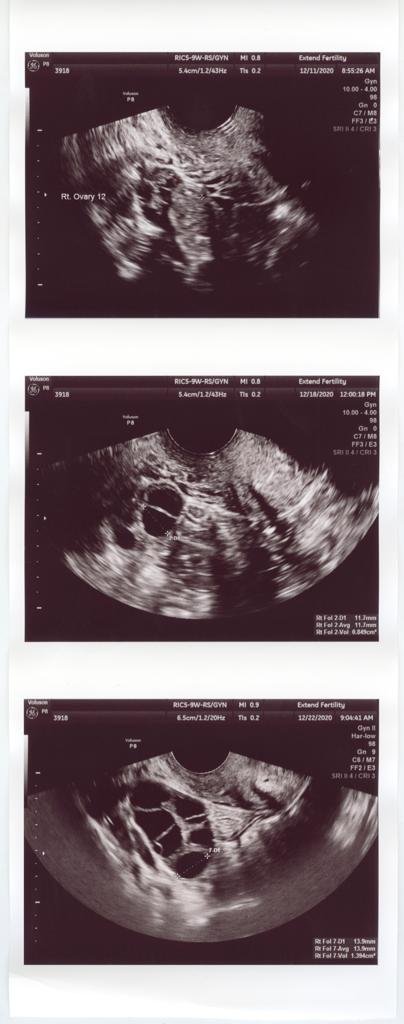

In “Glass Eggs,” British photographer and documentary filmmaker Matilda Hay explores the phenomenon of egg freezing through the experiences, emotions, and motivations of women who have done it.

By juxtaposing the stark scientific process with the humanity of each woman involved, Matilda says this project aims to peel back the clinical facade and reveal the layers of complicated emotions beneath—from loss and ambiguous grief to resilience and hope; the pressure to have it all, and feelings of failure for not being where they thought they would be.

The photographer highlights how we still view fertility as a female burden for the female body—men are not faced with the same messaging, pressure, or anxiety. In 2019, 16,000 women in America froze their eggs and in 2020, clinics reported a 50% increase due to the pandemic. Although egg freezing is physically intense, prohibitively expensive—one cycle costs $10,000—and not guaranteed to work, this process can offer hope and empowerment to women in a situation that is otherwise beyond their control. Yet the fact that it’s becoming so expected feels like a slippery slope, a new unequal standard that women must live up to.